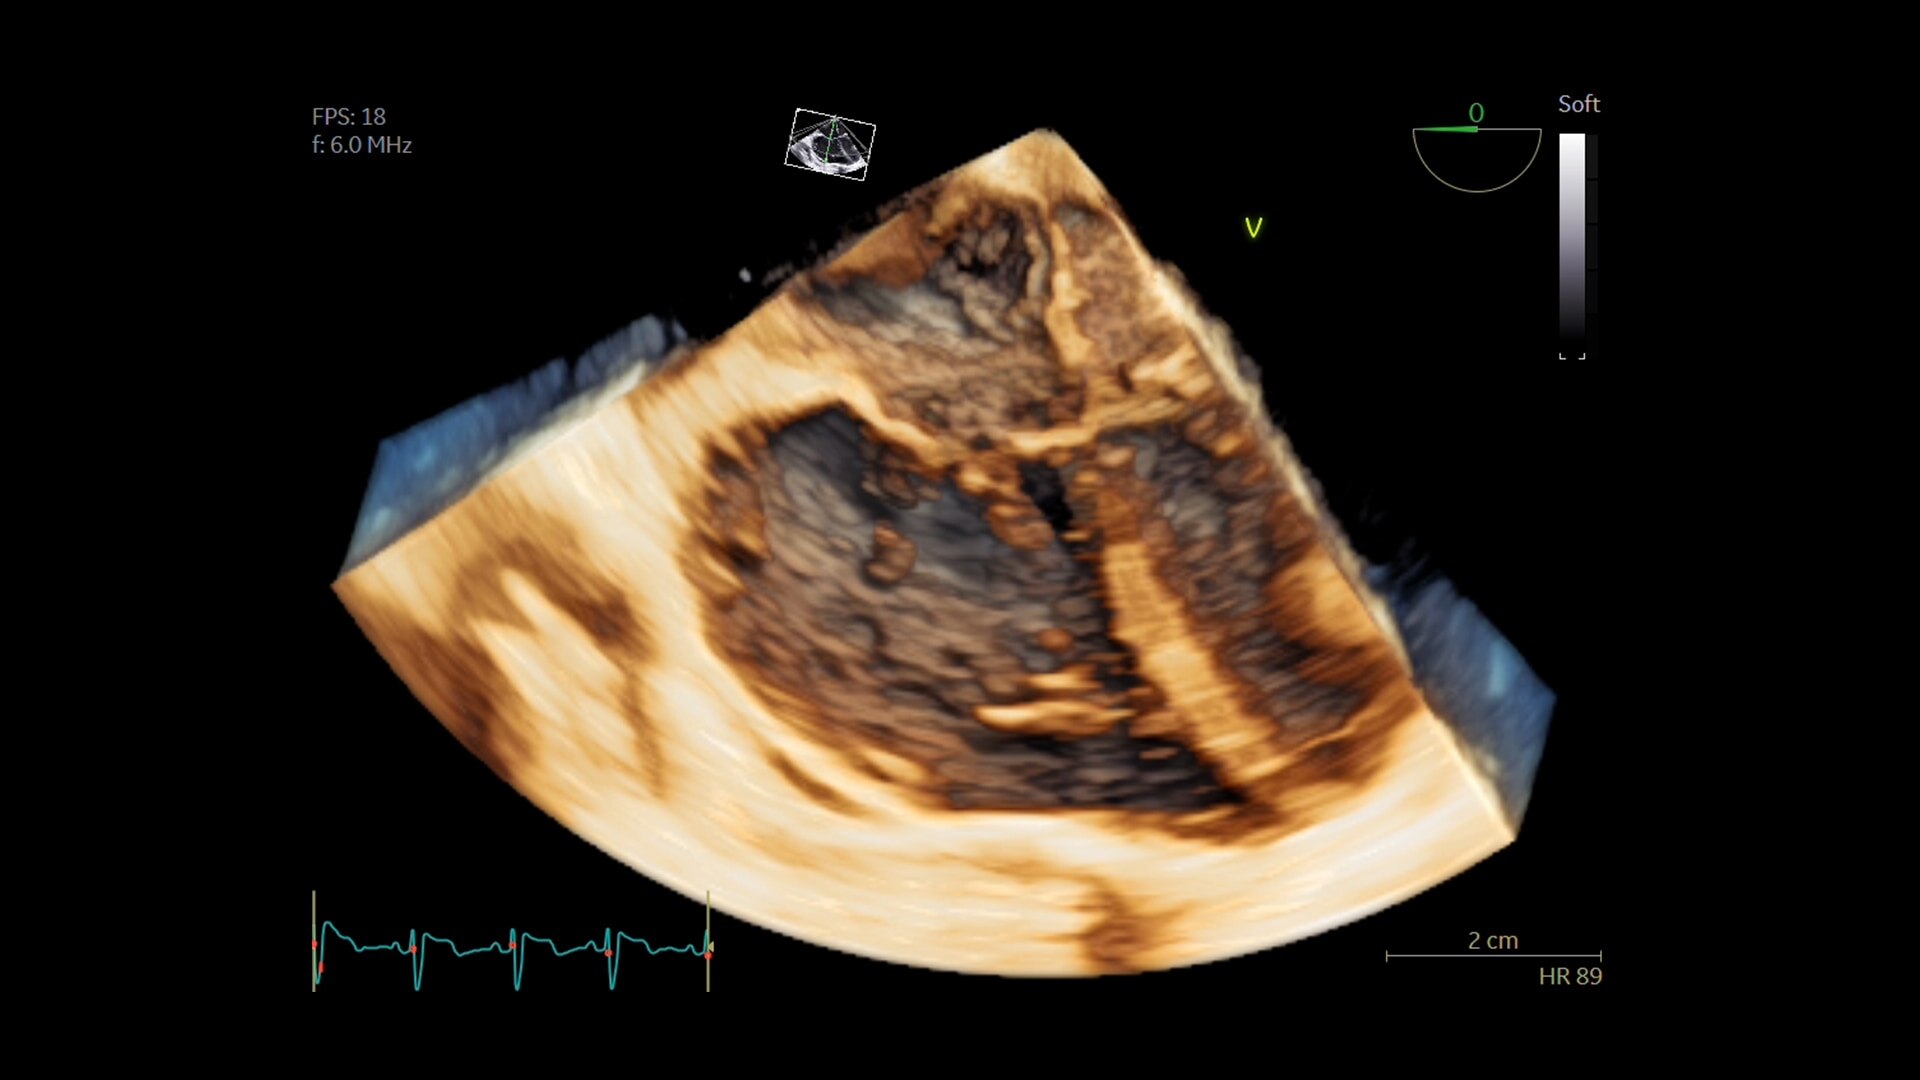

Üstün görüntü kalitesi

Daha net görüntüler daha kolay tanılar anlamına gelir ve derin öğrenme teknolojimiz AIR™ Recon DL ile olağanüstü kalitede görüntüleri daha hızlı elde edebilirsiniz. Çok çeşitli anatomiler için en net sonuçları sağlayarak MR görüntülerini görüntüleme biçiminizde devrim yaratır.

Ayrıca, göz yorgunluğunu azaltabilen okunması kolay, yüksek kaliteli taramalarla elde ettiğiniz görüntülerin kalitesinden daha emin olarak oluşturulan raporların daha iyi bir genel deneyime sahip olmasını sağlayabilirsiniz.